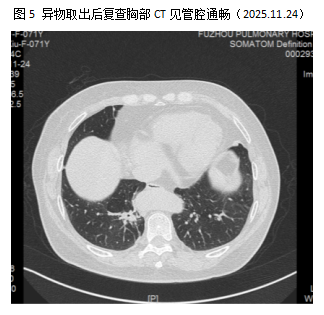

患者为71岁老年女性,因“咳嗽、胸闷 10 余天”入院,此前经当地抗感染治疗后症状未缓解,胸部CT检查提示右下叶支气管后基底段亚段存在可疑异物。由于异物嵌顿位置隐蔽,周围组织粘连,且操作空间狭小,对手术技术提出极高要求。医师团队与麻醉科联合研判后,制定全麻气管插管下电子支气管镜取异物的精准方案,并完善手术及应急处置预案。

异物取出瞬间,手术室内全员长舒一口气,疲惫的脸上露出欣慰笑容。术后患者恢复顺利,困扰多日的咳嗽、胸闷症状迅速缓解,不日即可康复出院。此次手术的成功,为医院积累了处理类似深部疑难气道异物病例的宝贵经验,也将为更多深受气道疾病困扰的患者带来康复曙光。